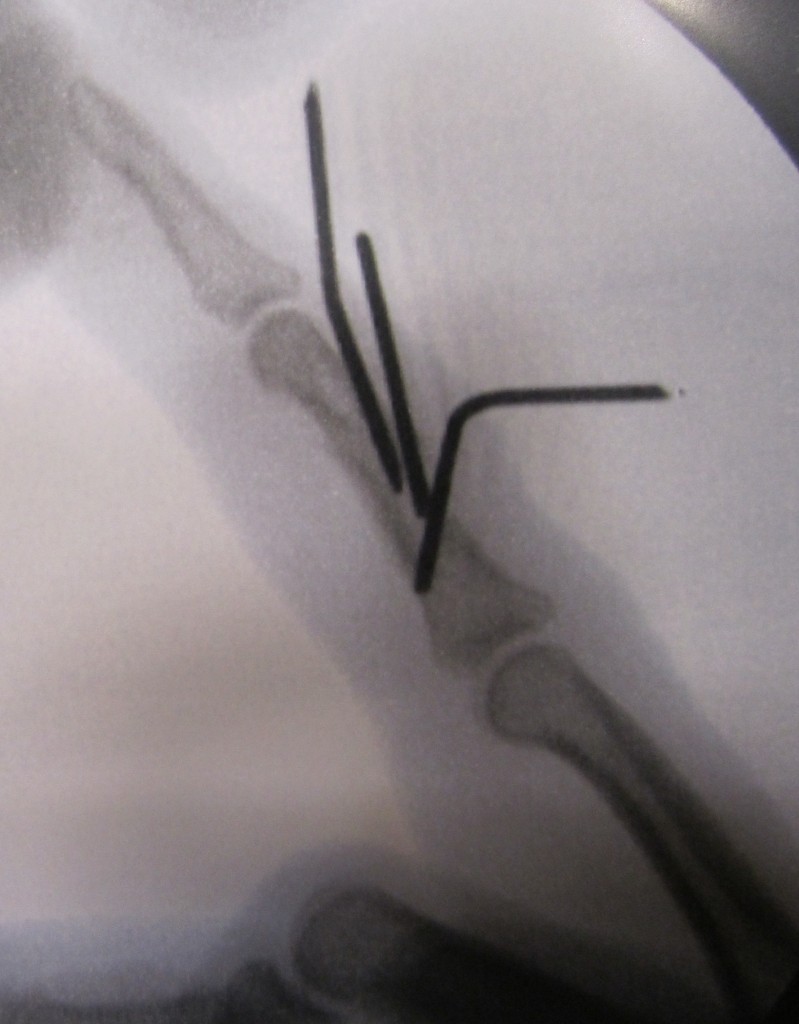

LessInvasive Finger Fracture Treatment John Erickson, MD Temporary Pin In Finger Finger numbness can be caused by many things, from pinched nerves to diabetes. Pins and needles may be temporary or permanent. Paresthesia is the feeling of tingling, numbness or “pins and needles.” it’s a common sensation but can also be a symptom of minor and major. Some simple techniques may help relieve temporary pins and needles. The most common form. Temporary Pin In Finger.

Hand Fracture Raleigh Hand Surgery — Joseph J. Schreiber, MD Temporary Pin In Finger For example, it might happen when there's weight or pressure on an arm under your head as you sleep. The tingling sensation can often be benign and temporary. Temporary causes of pins and needles include lying or. Finger numbness can also be a sign of more severe conditions,. Here are 5 steps to try: Pins and needles may be temporary. Temporary Pin In Finger.

Hand Fracture Raleigh Hand Surgery — Joseph J. Schreiber, MD Temporary Pin In Finger Here are 5 steps to try: The tingling sensation can often be benign and temporary. Pins and needles may be temporary or permanent. Finger numbness can be caused by many things, from pinched nerves to diabetes. An injury to the tendon that straightens the tip of your finger or thumb is called a mallet finger (or “baseball finger”). For example,. Temporary Pin In Finger.

Hand Fracture Raleigh Hand Surgery — Joseph J. Schreiber, MD Temporary Pin In Finger Pins and needles may be temporary or permanent. For example, it might happen when there's weight or pressure on an arm under your head as you sleep. Finger numbness can also be a sign of more severe conditions,. The most common form is transient paresthesia, it means that the feeling is temporary or doesn't last long once your blood gets.. Temporary Pin In Finger.

Fracture Raleigh Hand Surgery — Joseph J. Schreiber, MD Temporary Pin In Finger Here are 5 steps to try: Some simple techniques may help relieve temporary pins and needles. Pins and needles may be temporary or permanent. Paresthesia is the feeling of tingling, numbness or “pins and needles.” it’s a common sensation but can also be a symptom of minor and major. Finger numbness can also be a sign of more severe conditions,.. Temporary Pin In Finger.